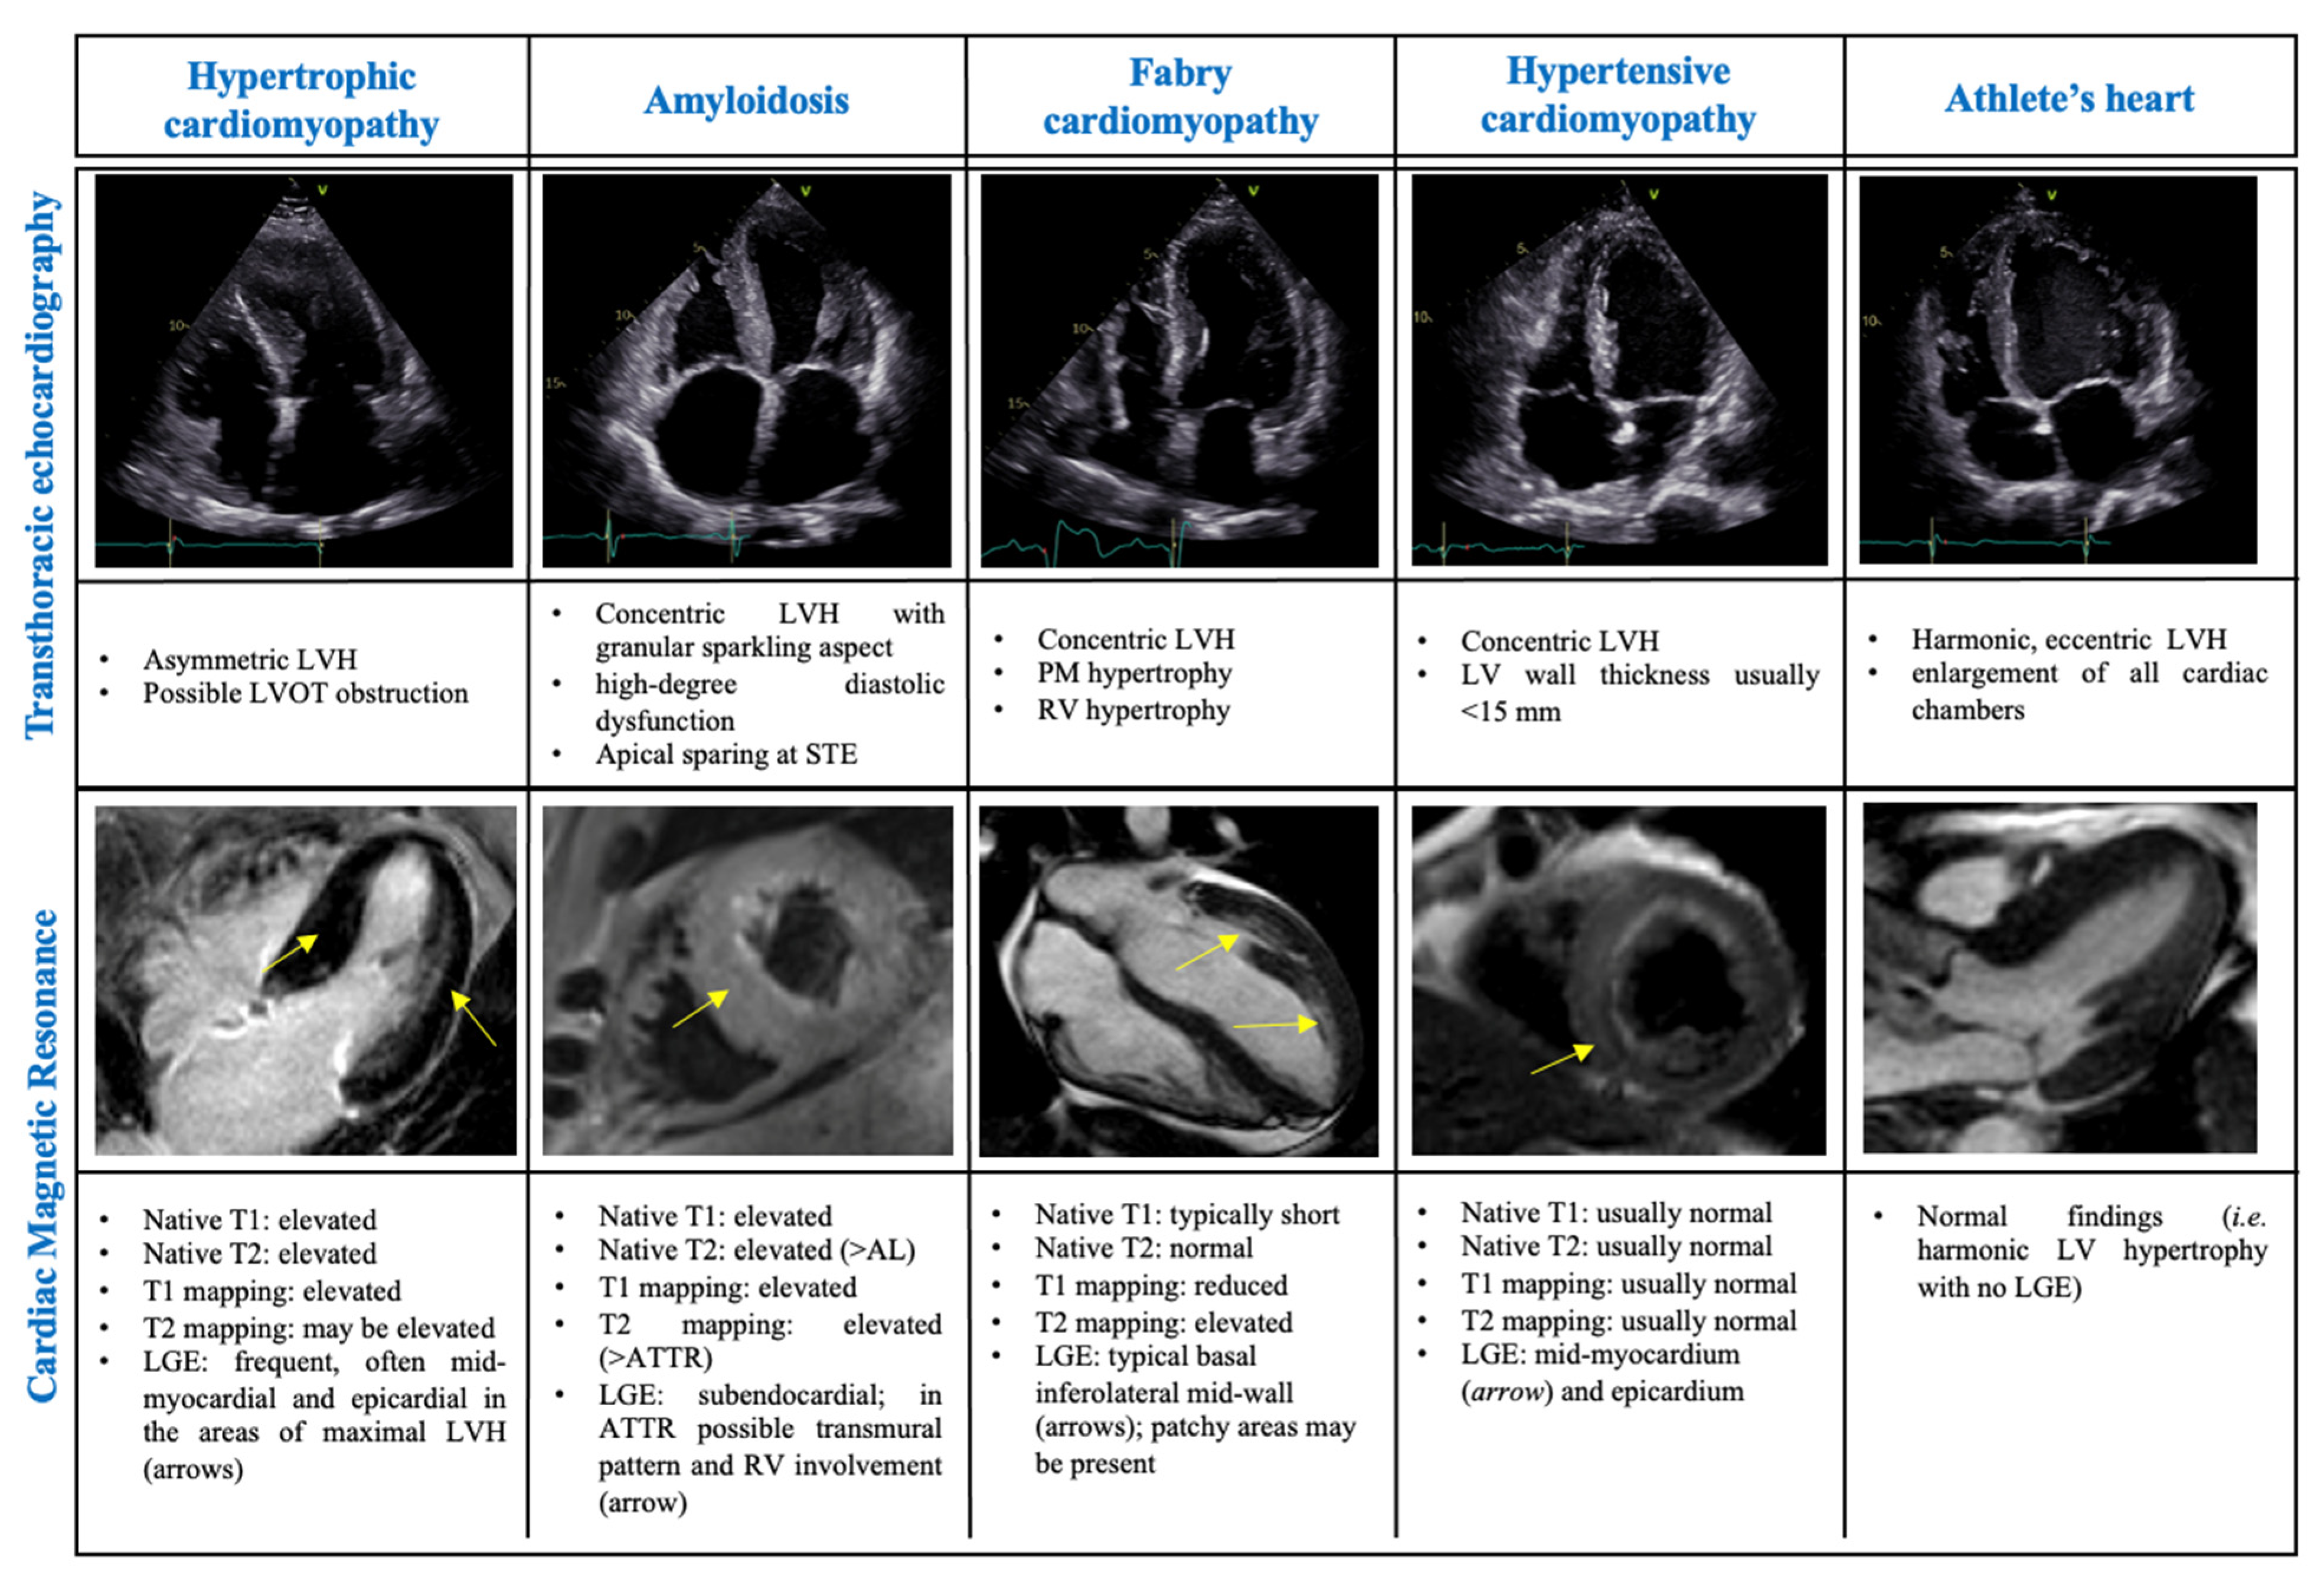

3.1. Differential Diagnosis of Phenocopies

3.1.1. The Athlete’s Heart

3.1.2. Amyloidosis

3.1.3. Hypertensive Cardiomyopathy

3.1.4. Fabry Cardiomyopathy